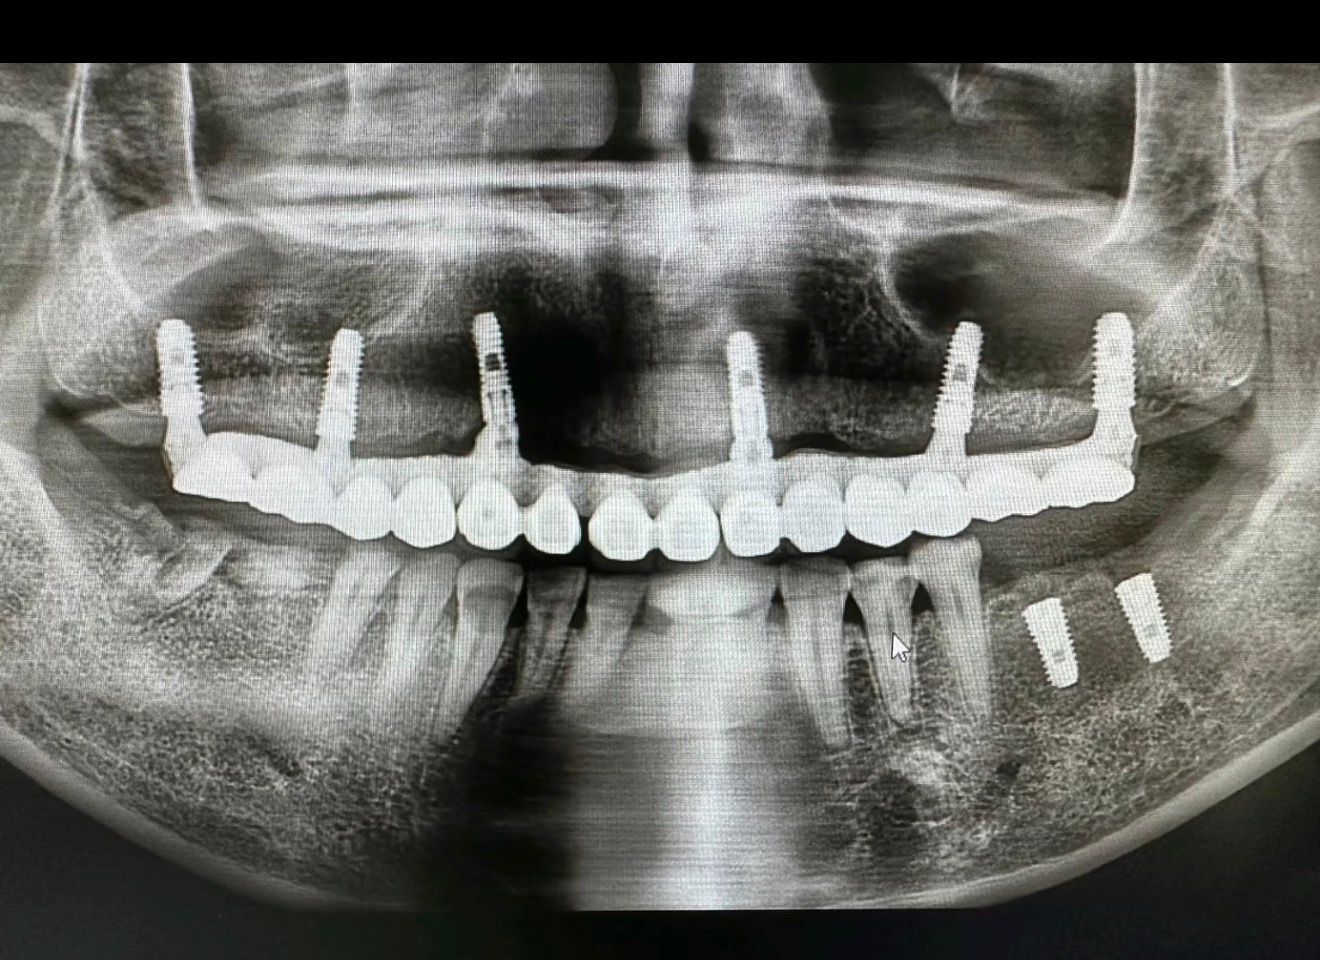

Примеры имплантации зубов в Хуньчуне